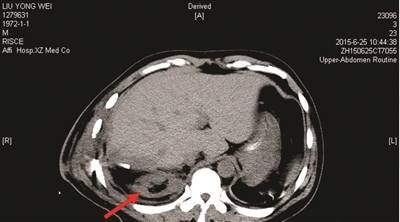

图二 2015年6月25日(术后第5天)CT,右肾如箭头所示。

2016年5月5日下午,徐州市卫生计生委组成调查组展开调查,专家组初步意见如下:患者为车祸导致的多发性骨折、肝及右肾挫伤等复合型外伤,在当地医院救治后转至徐医附院,在徐医附院术后第一天、第五天的CT检查均显示右肾存在。初步判断存在右肾损伤后血液供应障碍引起肾萎缩的可能性,需要对患者进行进一步检查。